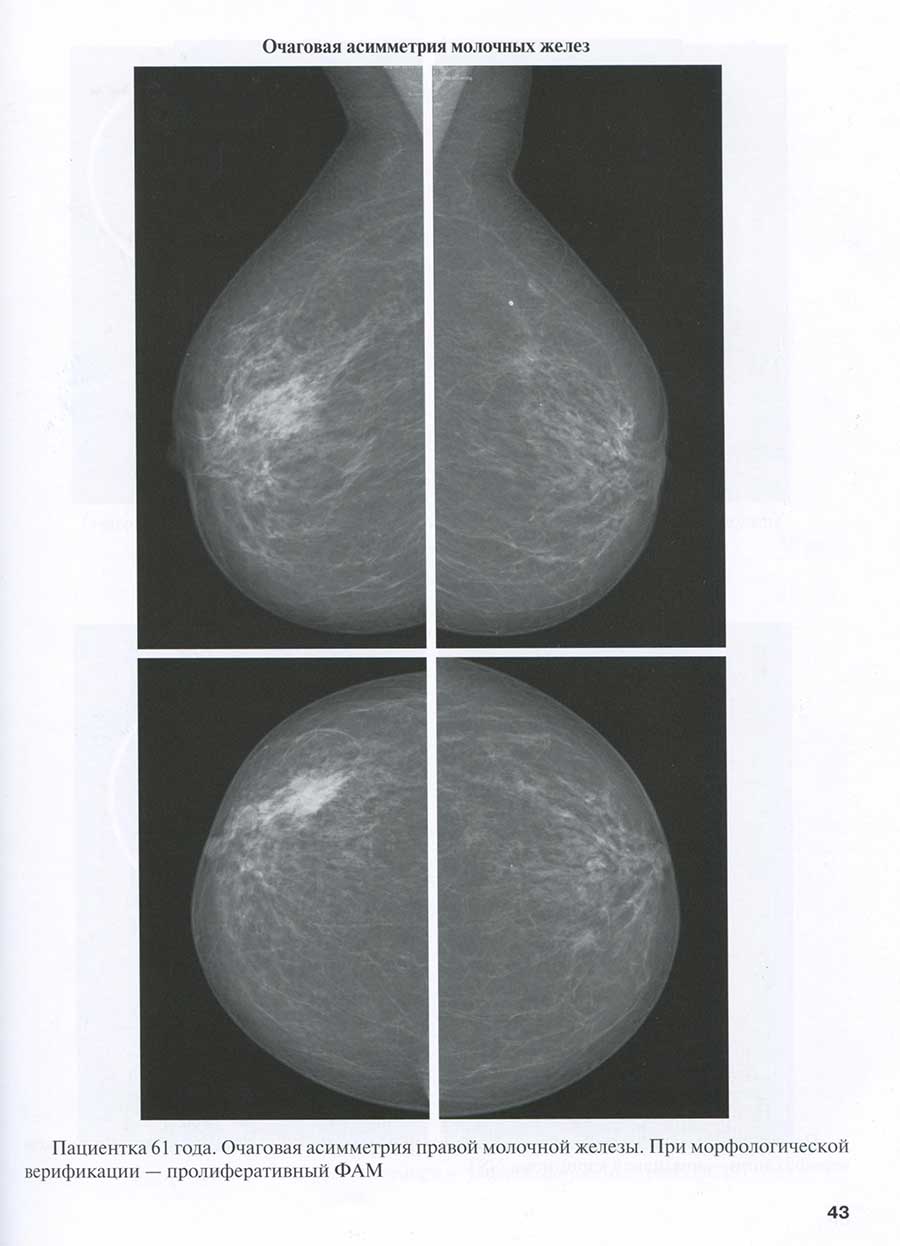

Очаговая асимметрия